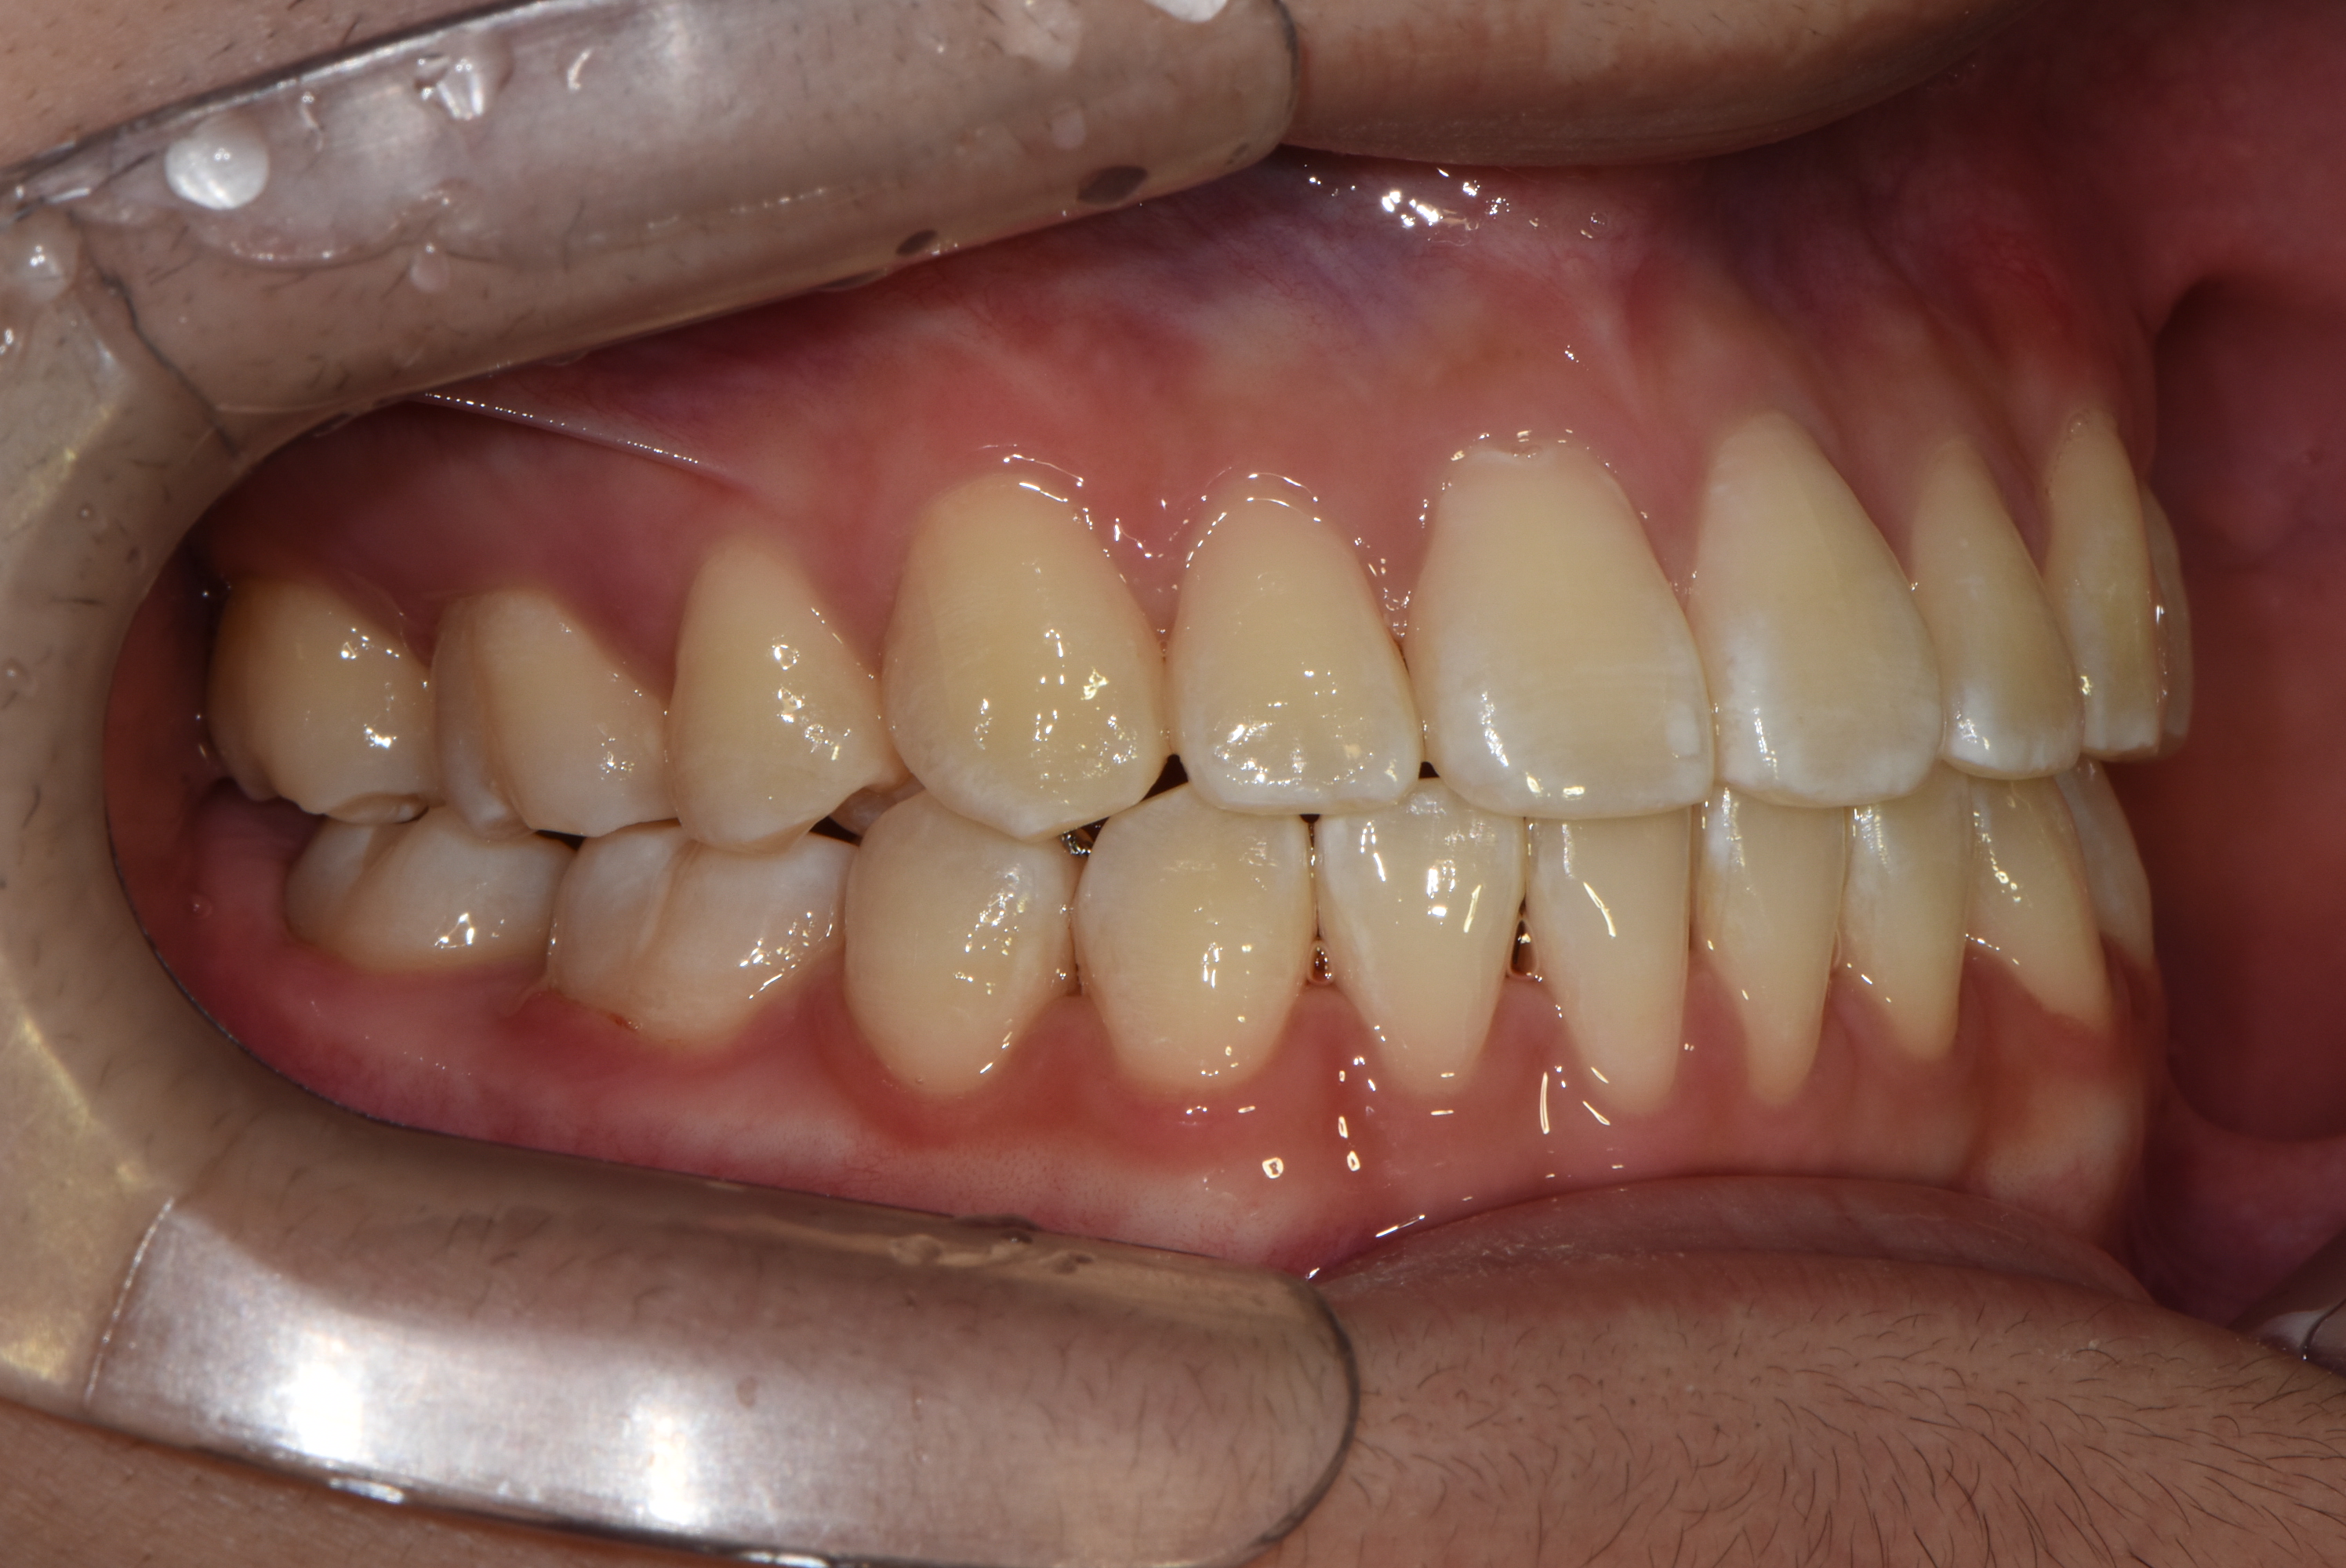

치료 전 사진입니다.